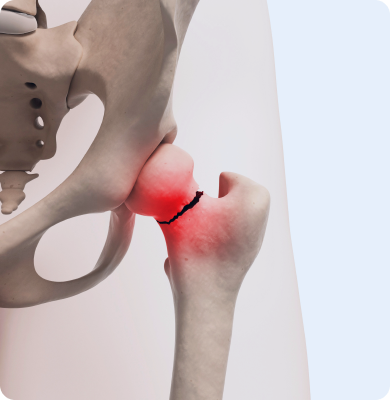

퇴행성 고관절염

고관절의 연골이 서서히 닳아 없어지면서 관절의 기능이 저하되고 통증을 유발하는 질환

주요원인

나이가 들면서 자연스럽게 연골이 닳아 발생하며 비만이나 과체중, 고관절 부상, 선천적인 고관절 기형 등이 주요 원인입니다.

주요증상

• 고관절 부위에 지속적인 통증이 발생하며 활동 시 통증이 심해집니다.

• 걷거나 계단을 오를 때 통증이 더 심해지고 다리의 움직임이 제한될 수 있습니다.

• 통증으로 인해 관절의 움직임이 둔해지고 때로는 엉덩이나 허벅지로 방사되는 통증이 나타날 수 있습니다.